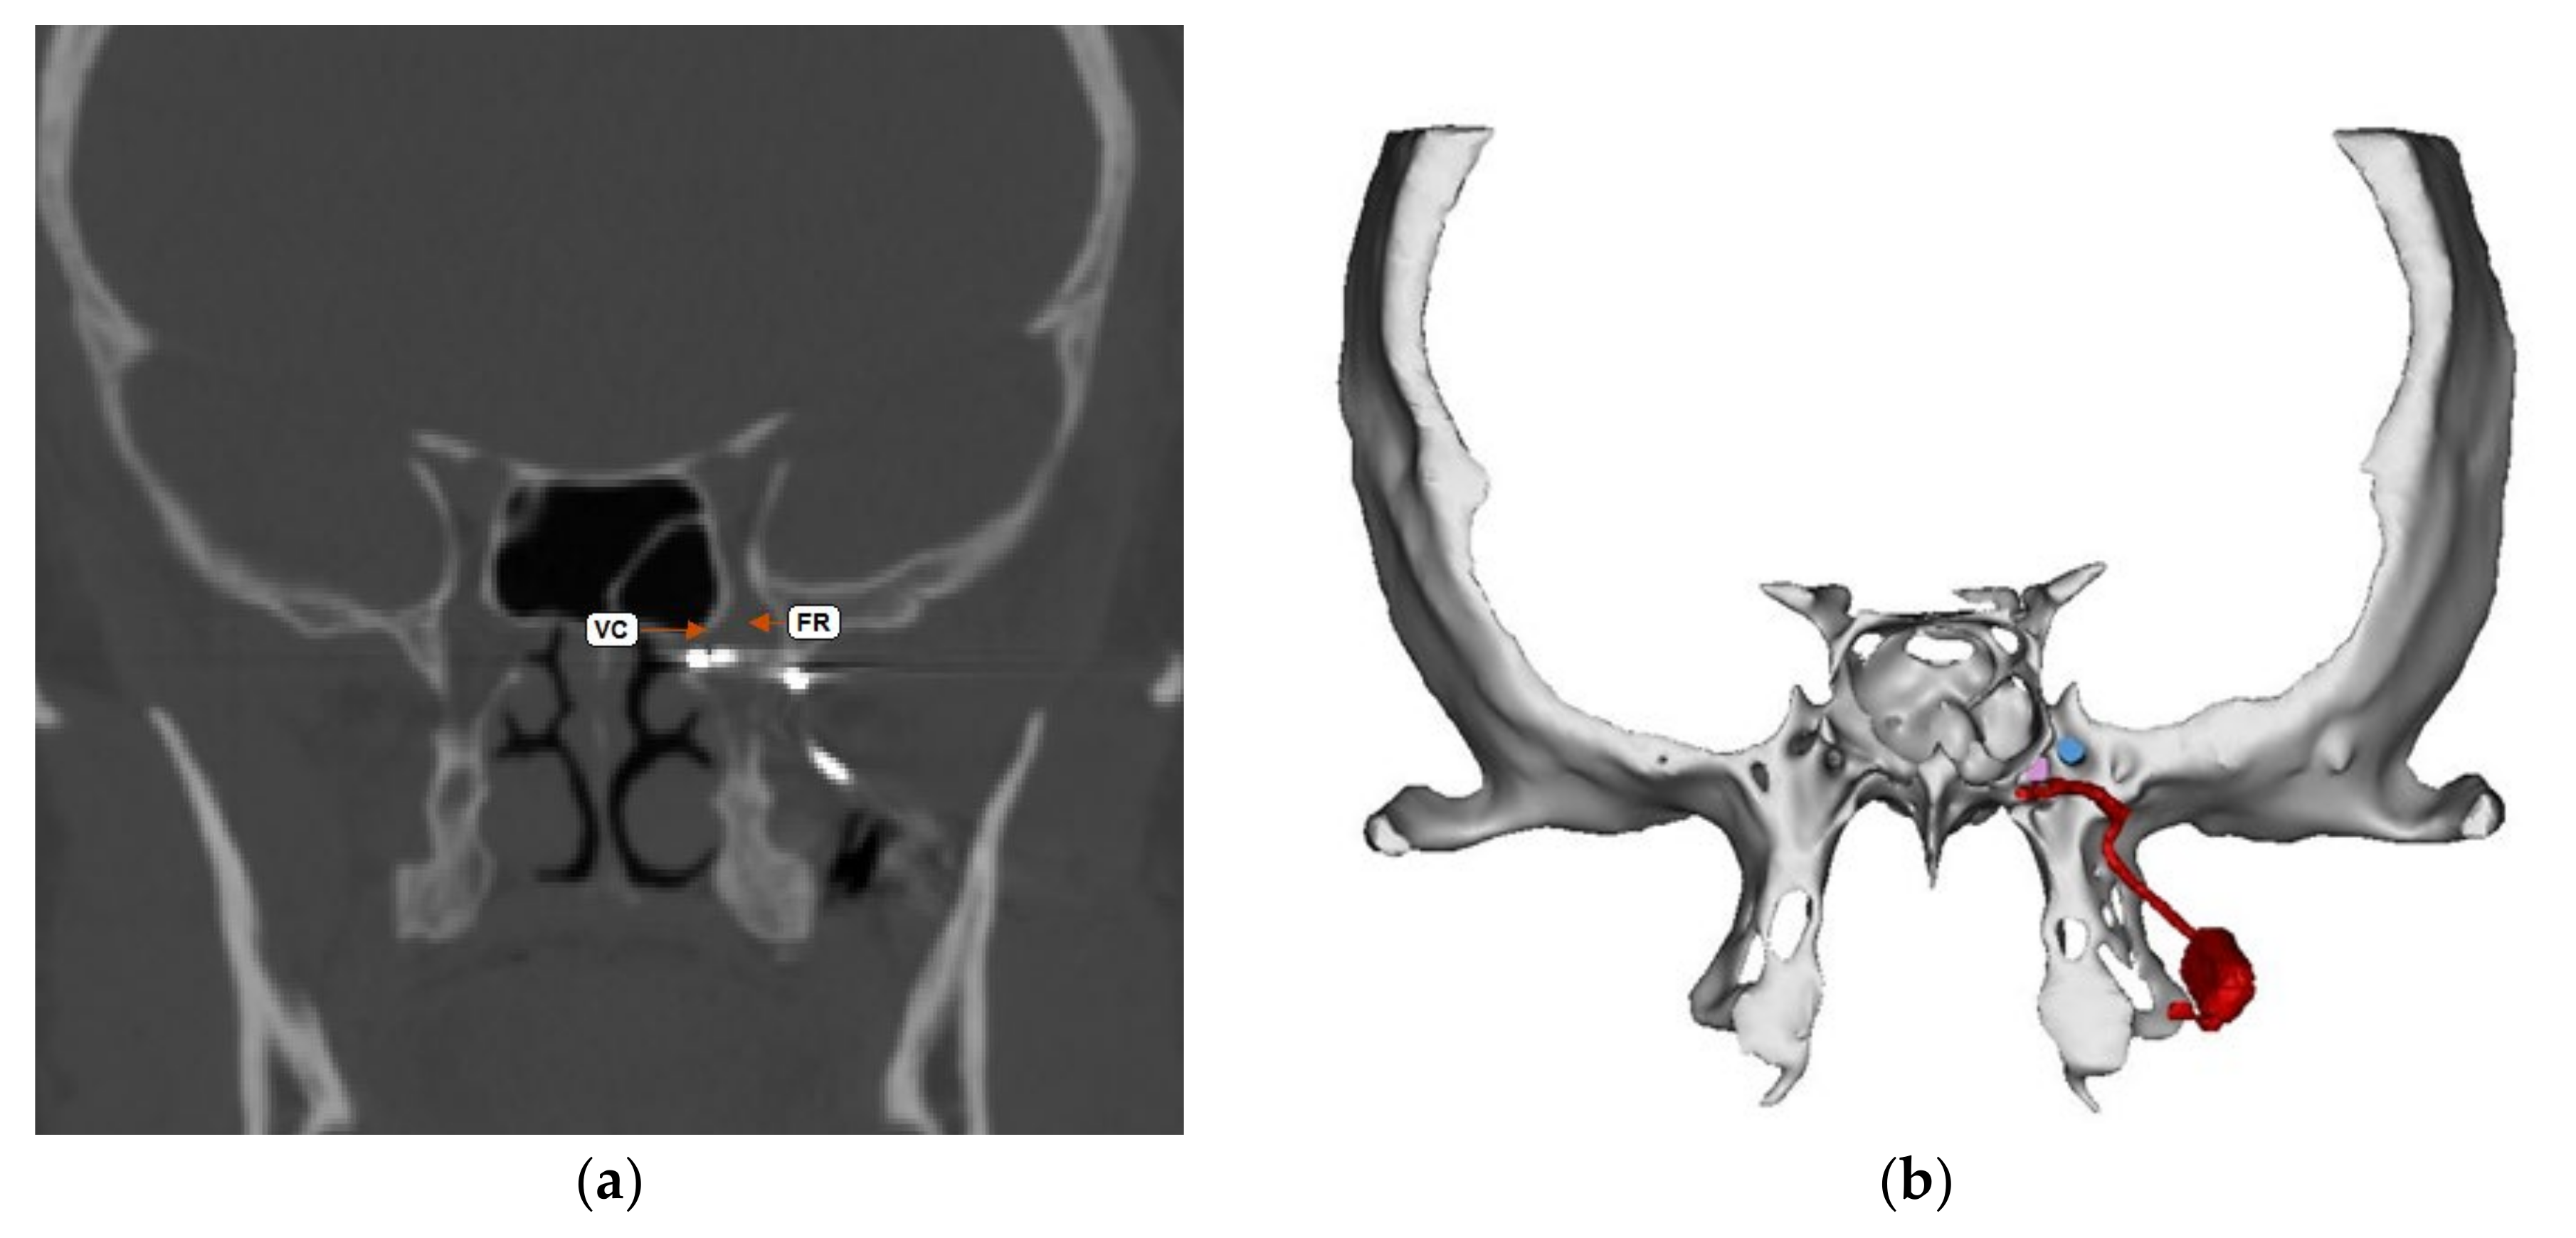

The Pathway CH-2 clinical trial “Sphenopalatine Ganglion Stimulation for Treatment of Chronic Cluster Headache” was an FDA approved study sponsored by Autonomic Technologies, Inc. (ATI), commencing in 2014. It was a multi-center, interventional, randomized, placebo-controlled, parallel, triple-blind safety and efficacy study that included intra-operative procedures for the implantation of the ATI-Neurostimulator in the pterygopalatine fossa so that an active electrode was within 0.5 mm of the sphenopalatine ganglion to intercept cluster headache symptoms at the onset. Each patient signed informed consent approved by the UTSW IRB committee (STU#052015-044). The results of this clinical trial have been previously published [16]. The sphenopalatine ganglion is located at the terminal end of the vidian canal, which contains the greater and lesser petrosal nerves that are preganglionic parasympathetic afferents synapsing in the sphenopalatine ganglion, which are shown to be involved in inducing the trigeminal autonomic reflex onset of cluster headaches [17]. Thus, stimulating the sphenopalatine ganglion would intercept this interaction and terminate the cluster headache. Figure 1 shows a coronal CT scan and adjacent illustration showing the position of the vidian canal (VC) in the medial portion of the pterygopalatine fossa. Just lateral to the VC is the foramen rotundum (FR), which contains the main trunk of the trigeminal maxillary division (V2). The CT view shows visible electrodes properly positioned to stimulate the sphenopalatine ganglion, and the illustration shows the trajectory of the implant close to FR and the transmitter connection on the lateral maxilla. Implantation of the ATI-Neurostimulator is performed through a small surgical incision through the maxillary posterior mucosa to expose the base of the zygoma and the pterygomaxillary plate. An introducer is used to position the implant at the sphenopalatine ganglion site under fluoroscopy. Figure 2 shows an illustration of the introducer device used to position the ATI-Neurostimulator. The electrodes are inactive during placement and only stimulated after the implant has been fixated. The TCR events precede activation, thus, the proposed mechanism of TCR induction is a mechanical interaction with V2 near the FR during use of the introducer device and subsequent positioning of the implant for fixation. Figure 3 shows a lateral CT view of an ATI-Neurostimulator after fixation.

Figure 1. Coronal CT and illustration of the ATI-Neurostimulator in the pterygopalatine fossa with the terminal electrode within 0.5 mm of the sphenopalatine ganglion at the vidian canal (VC). The location of the foramen rotundum (FR) is shown in close proximity and lateral to the VC. (a) Shows CT image and terminal electrodes in proper position. (b) Shows illustration of A showing the position of the electrodes and the stimulators components on the lateral posterior maxilla.